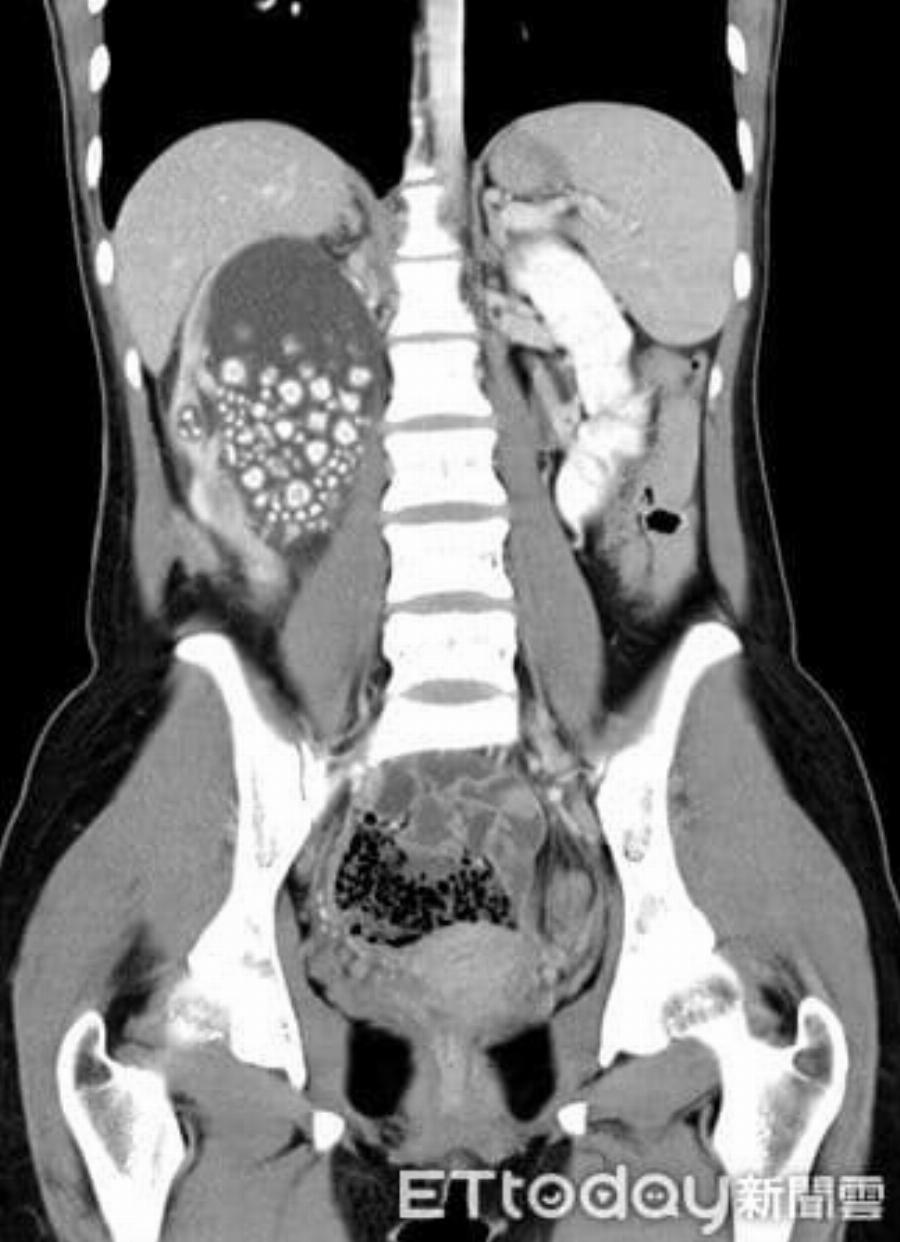

Η νεαρή γυναίκα άρχισε να νιώθει έντονη κόπωση, πυρετό και πόνους στη μέση. Οι γιατροί αρχικά υποψιάστηκαν λοίμωξη του ουροποιητικού ή φλεγμονή των νεφρών — καταστάσεις που αντιμετωπίζονται εύκολα. Όμως οι αξονικές και υπερηχογραφικές εξετάσεις αποκάλυψαν κάτι απίστευτο: το δεξί της νεφρό ήταν διογκωμένο και φραγμένο με εκατοντάδες πέτρες σαν μεγάλους κόκκους άμμου σχεδόν δύο εκατοστών.

Οι περισσότεροι ασθενείς έχουν έναν ή δύο πέτρες. Η νεαρή αυτή γυναίκα είχε εκατοντάδες, που συσσωρεύονταν επί χρόνια λόγω αφυδάτωσης, μέχρι που το σώμα της κατέρρευσε. Οι πέτρες είχαν μπλοκάρει το σύστημα διήθησης των νεφρών, προκαλώντας λοίμωξη και πυρετό.

H ακτινογραφία με τις πέτρες πάνω αριστερά